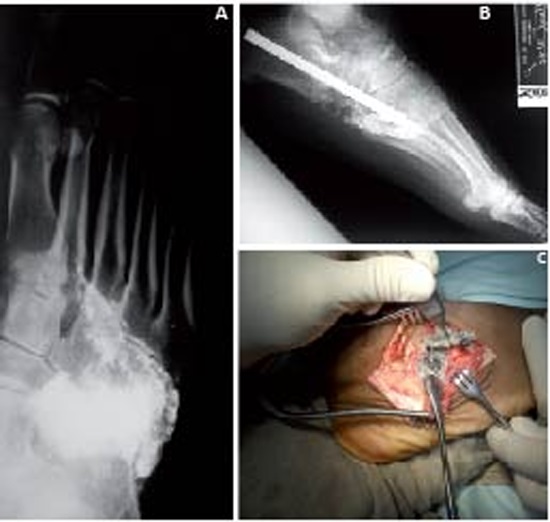

Blood smear (-). HIV (-). Rated by Internal Medicine and Neurology with a diagnostic impression of: Viral myelopathy, Guillain-Barré sequelae. Radiographs show presence of multiple fragments of lead in the sidebar of the foot with partial destruction of the Cuboids (Fig. 1A).

We considered the possibility of lead poisoning. Blood lead levels were taken and reported as 62 ug / dL (Normal: 0-9.9). Starting chelation therapy with EDTA: administered 50 mg/kg/day.

After chelation therapy, the patient was taken to surgery for removal of the bullet material and midfoot reconstruction (Figs. 1B-C).